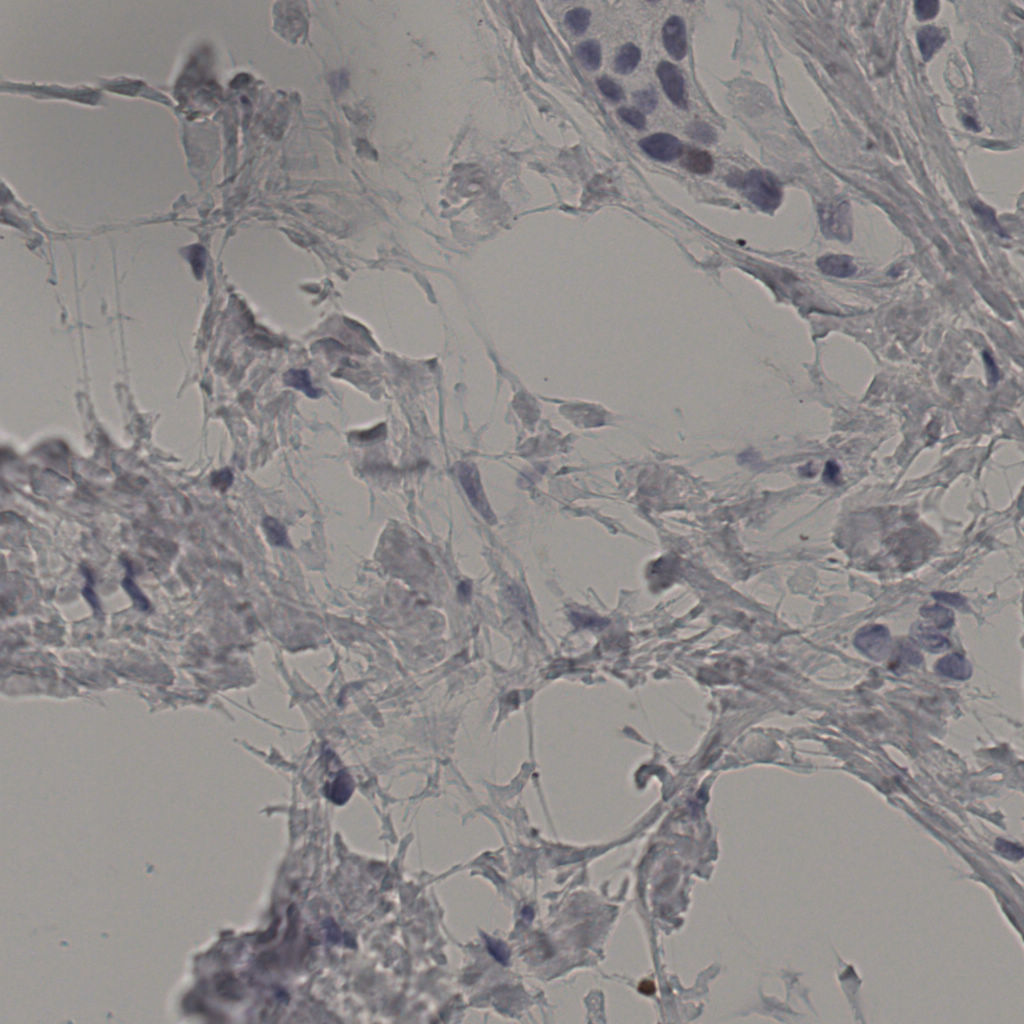

5.31%

Ki67 指数

阴 19502

阳 1093

切片统计

总切片

2970

有效

554

已标记

有效率

19%

标记后

标记前